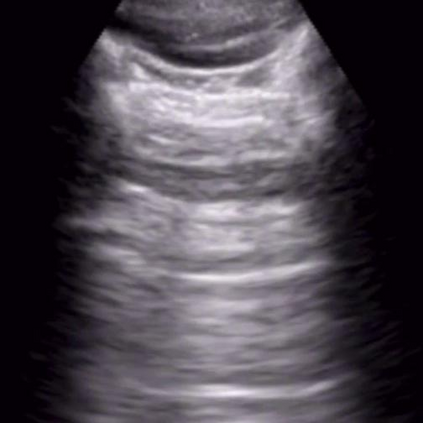

Most deep neural networks (DNNs) based ultrasound (US) medical image analysis models use pretrained backbones (e.g., ImageNet) for better model generalization. However, the domain gap between natural and medical images causes an inevitable performance bottleneck. To alleviate this problem, an US dataset named US-4 is constructed for direct pretraining on the same domain. It contains over 23,000 images from four US video sub-datasets. To learn robust features from US-4, we propose an US semi-supervised contrastive learning method, named USCL, for pretraining. In order to avoid high similarities between negative pairs as well as mine abundant visual features from limited US videos, USCL adopts a sample pair generation method to enrich the feature involved in a single step of contrastive optimization. Extensive experiments on several downstream tasks show the superiority of USCL pretraining against ImageNet pretraining and other state-of-the-art (SOTA) pretraining approaches. In particular, USCL pretrained backbone achieves fine-tuning accuracy of over 94% on POCUS dataset, which is 10% higher than 84% of the ImageNet pretrained model. The source codes of this work are available at https://github.com/983632847/USCL.